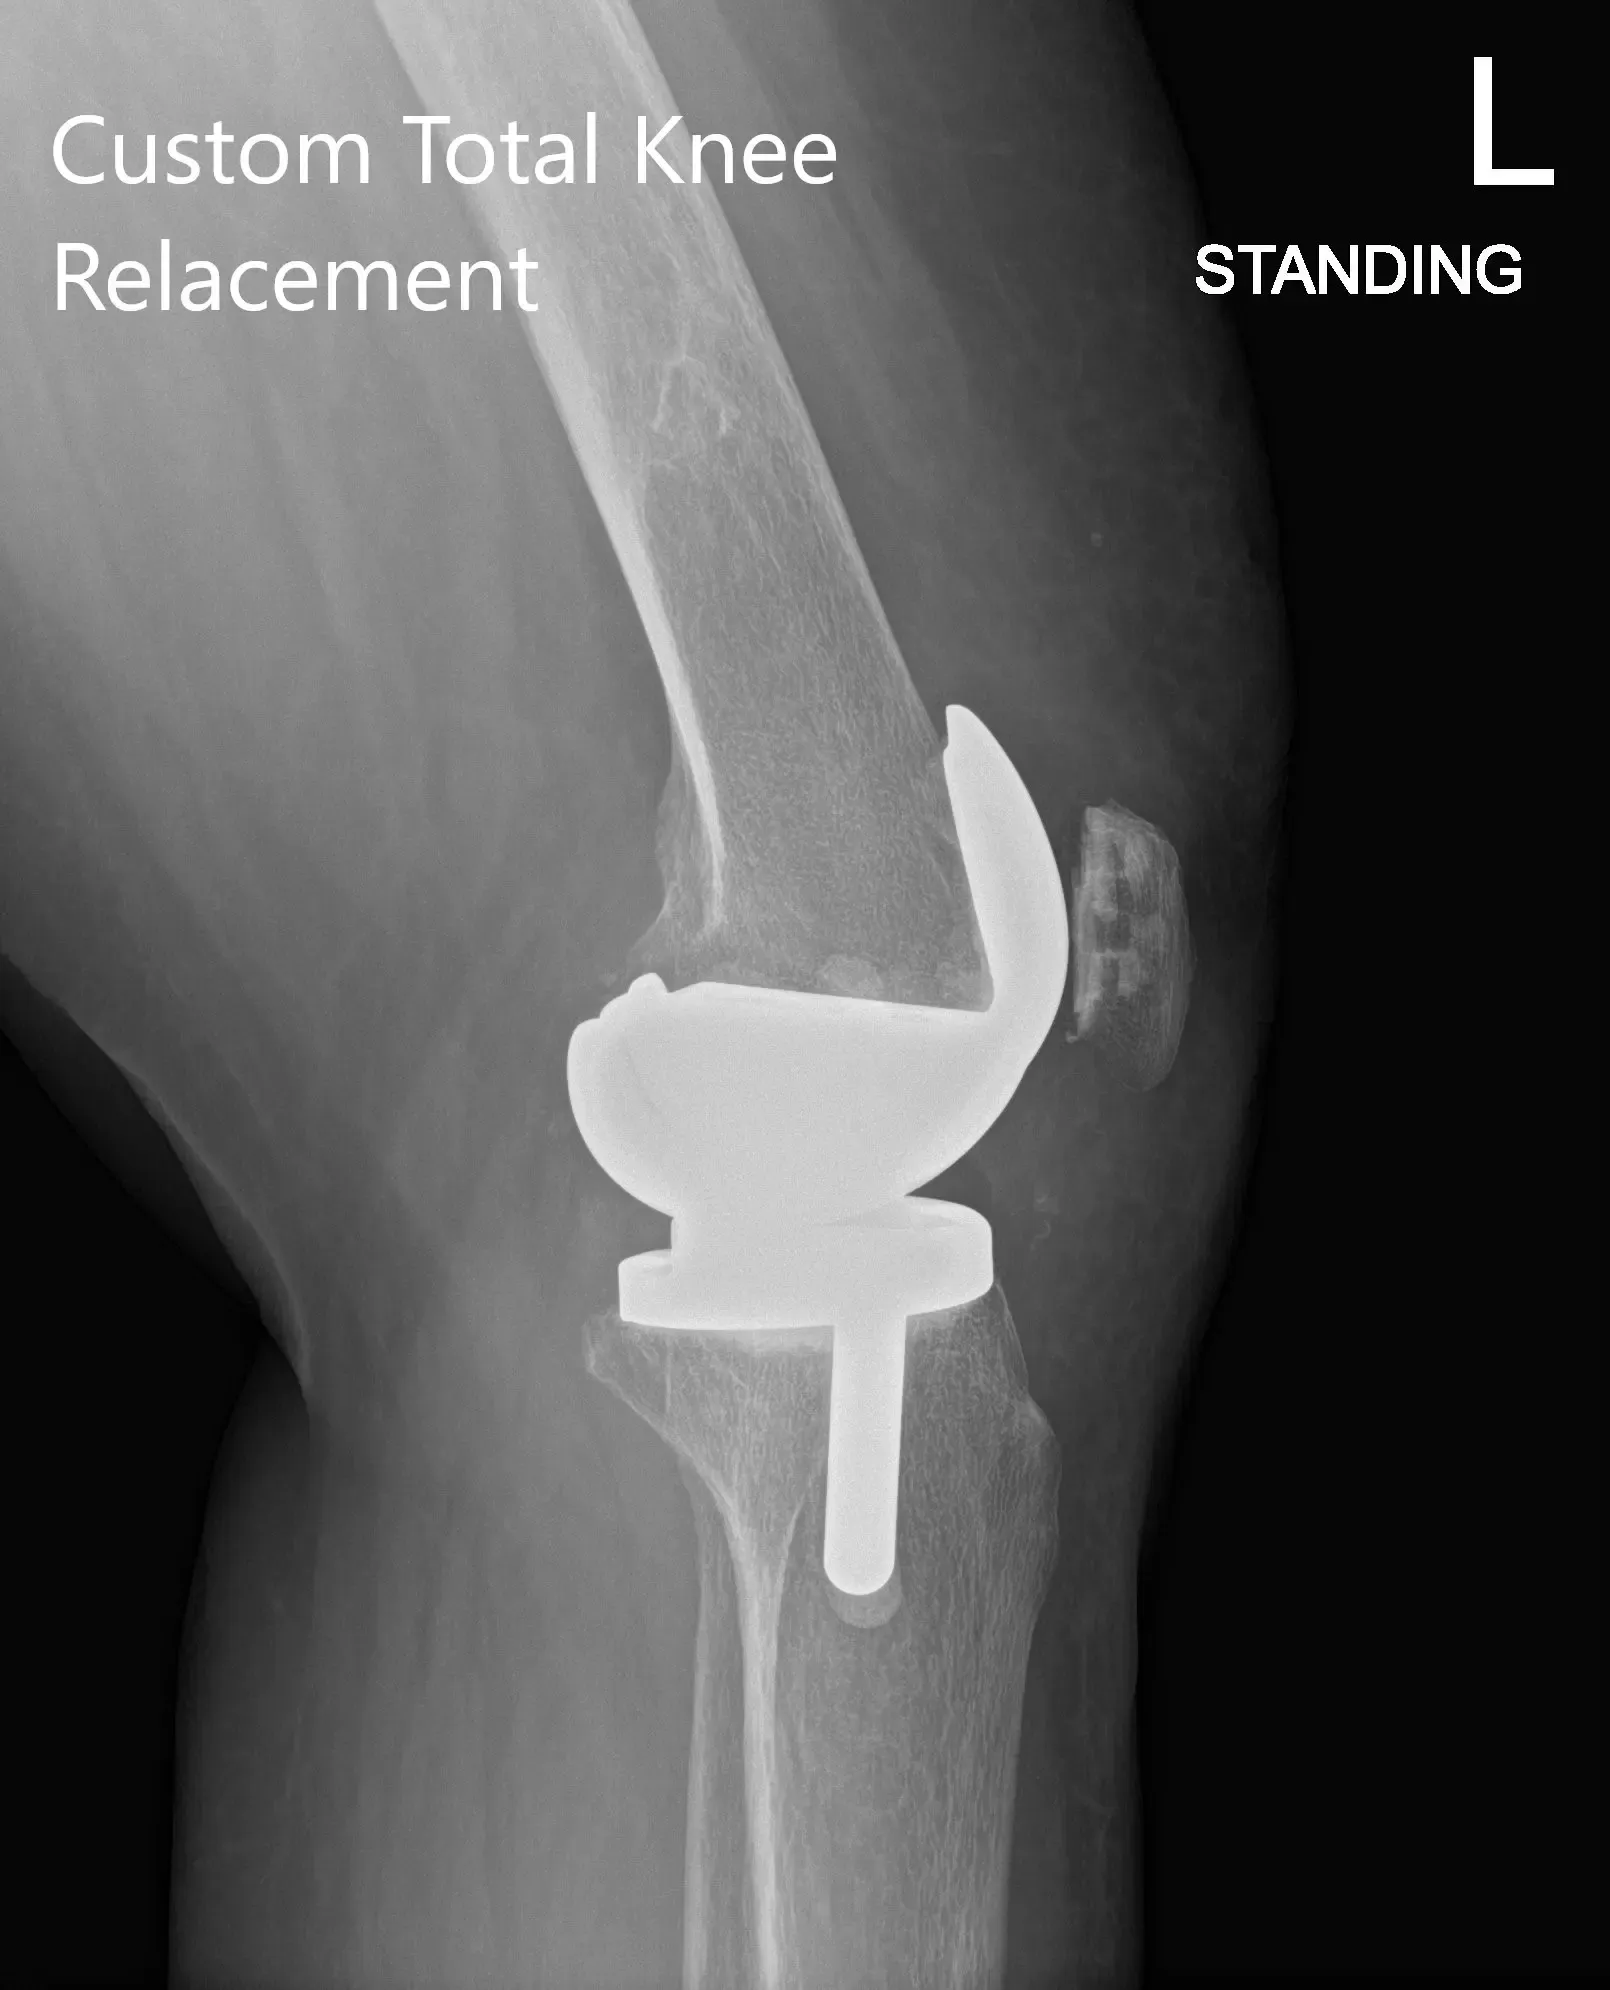

Radiografía postoperatoria que muestra PA y vista lateral de la rodilla izquierda

IMPLANTES UTILIZADOS: Fémur personalizado con tibia personalizada con polietileno estabilizado posterior y inserto rotuliano de 29 mm.

Luego se resecó la rótula. Se hicieron agujeros de perforación en la rótula. La rótula de prueba fue colocada en su lugar. El fémur de prueba se colocó en su posición y se preparó el resto de la tibia. A continuación, se colocó una tibia de prueba. El poliuretano se colocó en su posición y luego se redujo la rodilla. La rodilla fue puesta a prueba mediante todo un rango de movimiento. Había una estabilidad excelente. El seguimiento de la rótula fue excelente. Se logró una extensión completa y una flexión total durante la operación.